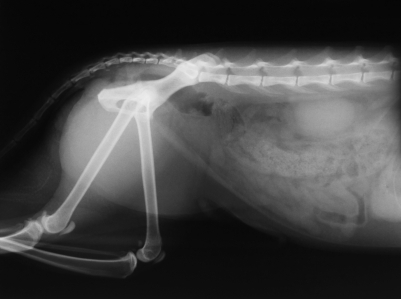

♦ צילומי רנטגן

צילום רנטגן של כלבמכשיר הרנטגן מאפשר לערוך הדמיה של מערכת השלד  (עצמות, חוליות, צלעות...) ושל רקמות רכות (אברים בחלל הבטן ובבית החזה).

הצילום מאפשר אבחון פתולוגיות כגון: גידולים, הגדלות של איברים, דלקות ריאה ועוד...

ציוד הרנטגן כולל מכשיר רנטגן חדש, וכן מכונת פיתוח. כך ניתן לקבל צילומים בזמן קצר ובאיכות גבוהה.